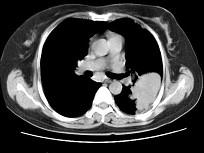

问题 女,52岁,左侧背痛1月,胸部CT如图,最可能的诊断为 ( )

选项 A.左肺中央型肺癌 B.左肺周围型肺癌 C.左肺感染 D.左肺炎性假瘤 E.肺隔离征

答案 D